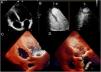

Varón de 57 años con antecedente de infarto de miocardio anterior. En una tomografía axial computarizada (TAC) cardíaca realizada 3 años más tarde, se objetiva una imagen hipodensa en el ápex del ventrículo izquierdo. Ante la sospecha de trombo, se completa el estudio mediante resonancia magnética cardíaca (RMC) con gadolinio, ecocardiografía transtorácica (ETT) 2D con ecopotenciador y ETT tridimensional. A través de la imagen multimodalidad se comprueba la ausencia de trombo.

Cardiac computed tomography showed a hypodense area in the apex of the left ventricle in a 57-year-old man with a history of anterior myocardial infarction three years earlier. To confirm or rule out a suspected thrombus, he underwent gadolinium-enhanced cardiac magnetic resonance imaging, contrast-enhanced two-dimensional transthoracic echocardiography, and three-dimensional transthoracic echocardiography. Multimodality imaging ruled out the presence of a thrombus.